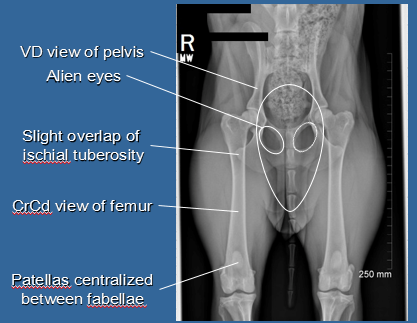

Which radiographic view is considered diagnostic for hip dysplasia?

VD view of pelvis

Hip extended view

Internal rotation of distal limbs